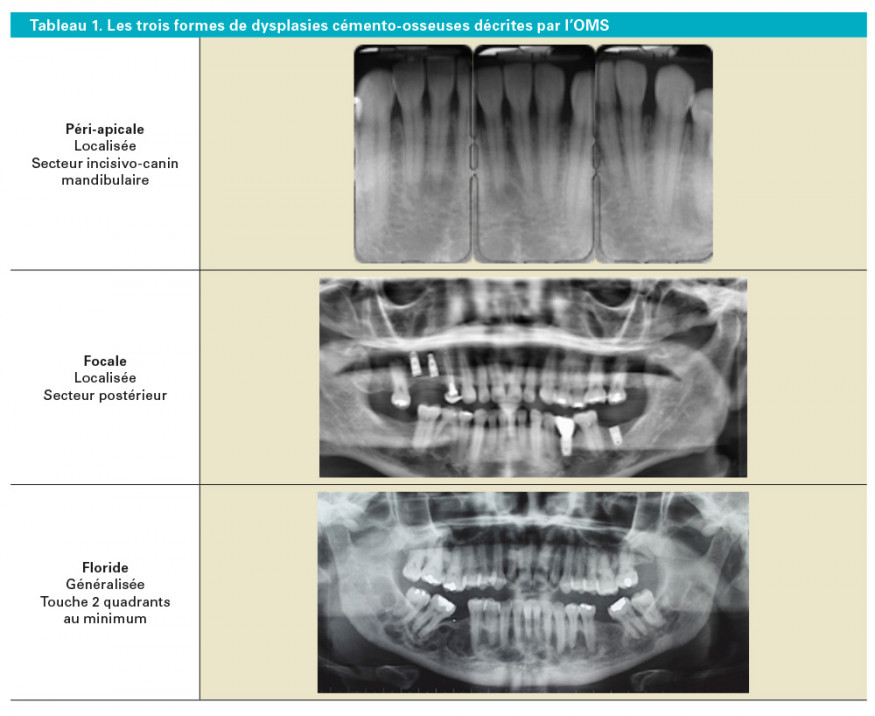

Selon l’Organisation Mondiale de la Santé (OMS) [3], trois formes de lésions partageant le même processus histopathologique sont retrouvées : péri-apicale, focale et floride (tableau 1).

Les formes péri-apicales et focales sont les plus fréquemment rencontrées [4] : elles sont caractérisées par des lésions de taille réduites, localisées, intéressant un petit nombre de dents. La dysplasie est dite péri-apicale lorsqu’elle intéresse le secteur incisif mandibulaire, focale si elle est localisée dans un secteur postérieur. La forme floride est plus extensive, plus ou moins bien limitée, intéressant au moins deux quadrants. Elle est caractérisée par des lésions multifocales lobulées, généralement bilatérales et symétriques. Cette forme floride peut être rencontrée à la mandibule comme au maxillaire.